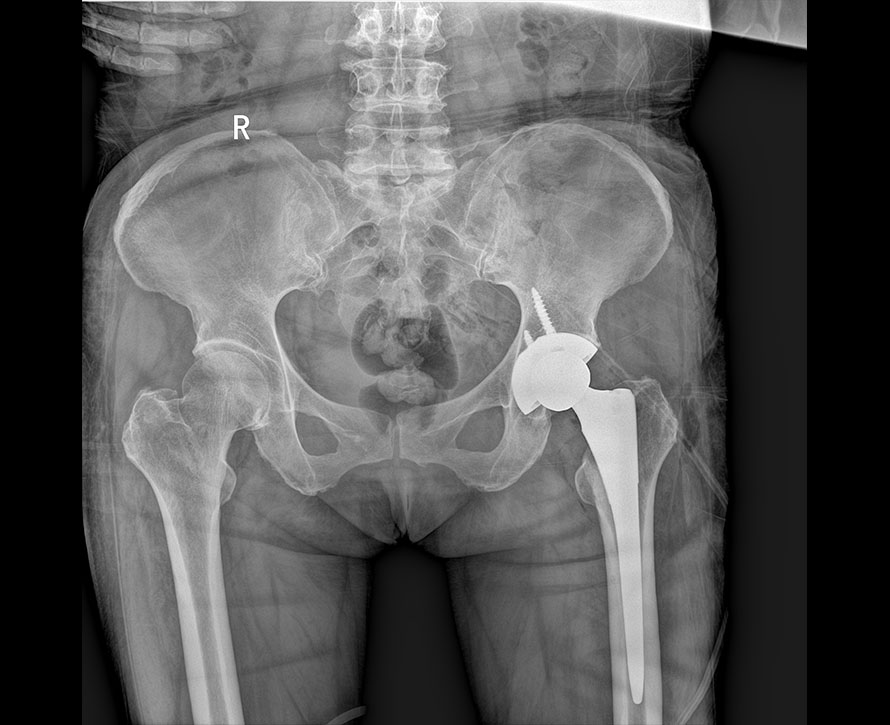

臨床圖像